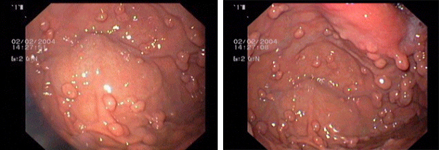

imagen1

Imagen endoscópica de un pólipo plano en el colon, antes (izquierda) y después de la resección